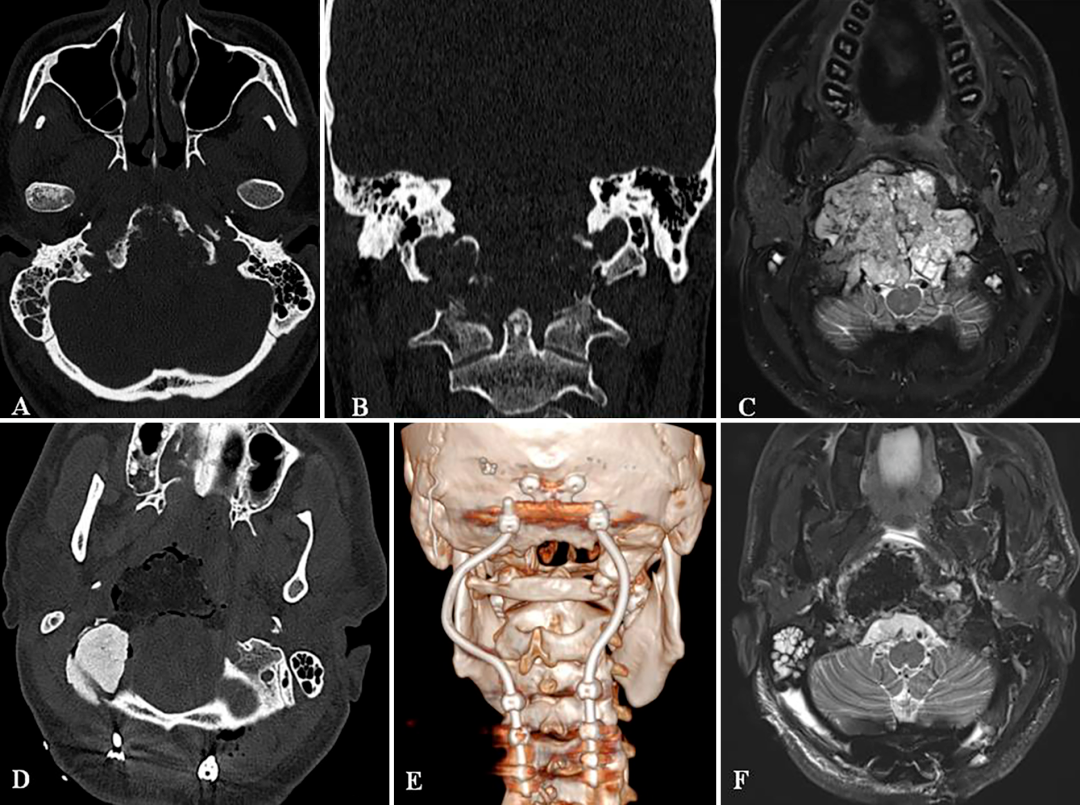

A和B

A和B:術(shù)前CT掃描顯示顱頸交接區(qū)脊索瘤,侵犯斜坡-枕髁并呈溶骨性破壞。C:術(shù)前MR顯示腫瘤巨大延伸,并浸潤長(zhǎng)入硬膜內(nèi)的腦實(shí)質(zhì)。D:術(shù)后CT顯示PMMA枕髁重建穩(wěn)定良好。E:術(shù)后三維CT顯示C0-C3-C4-C5枕頸融合穩(wěn)定,與根釘彎曲有利于PBRT治療。F:術(shù)后MR顯示全切腫瘤和腦干延髓占位壓迫得到解除。